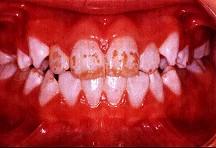

问题 关于氟斑牙的临床表现下列哪项不正确()

选项 A.同一时期萌出的釉质上有黄白相间斑块 B.重者并有釉质缺损 C.多见于乳牙和恒牙 D.对酸蚀的抵抗力强 E.对摩擦的耐受性差

答案 C